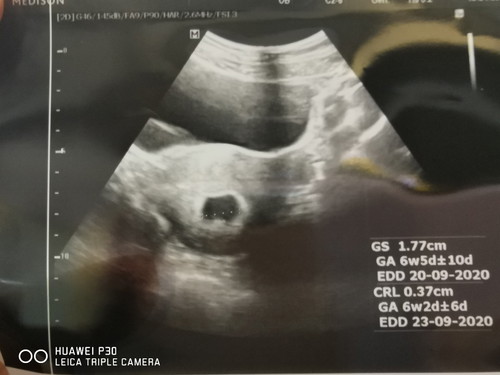

วันนี้ไปซาว ตามหมอนัด 7+4 week เเต่ในใบซาวได้ 6 wekk หมอบอกว่าน้องตัวเล็กลงกว่าอาทิตย์ก่อน ยังไม่เห็นหัวใจ โครโมโซมอาจผิดปกติ น้องมีโอกาสหลุด หมอนัดซาวอีกที 4 กพ. มีใครเป็นแบบเรามั้ยค่ะ... เศร้ามากๆเลย?